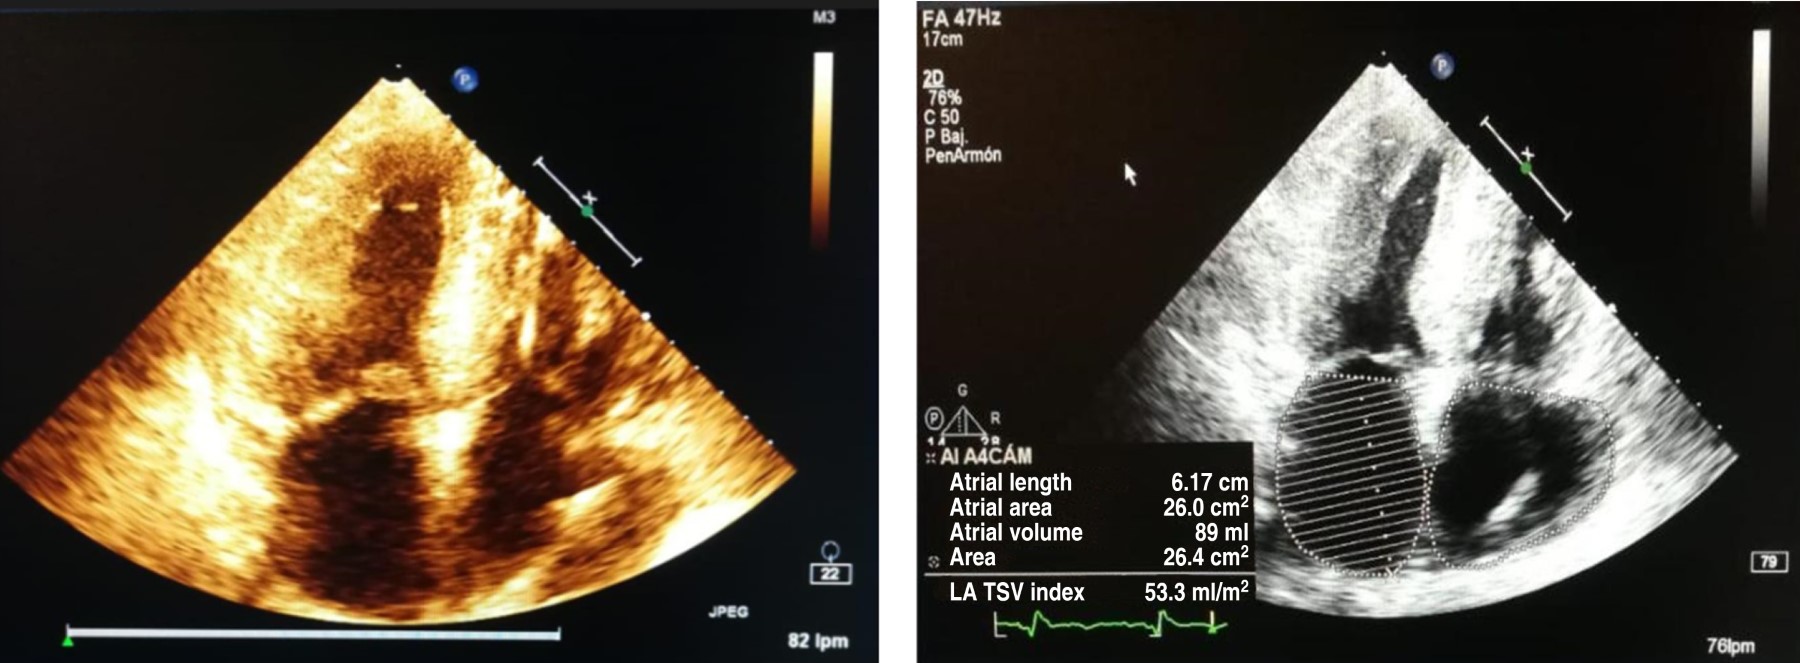

The patient first received symptomatic treatment with diuretics for dyspnea. An electrocardiogram (EKG) (Figure 1) and transthoracic echocardiogram (Figure 2) were performed for diagnosis.

The EKG showed Q waves in precordial leads from V1 to V4 with associated low voltage. The echocardiography showed a left ventricular ejection fraction (LVEF) of 48%, grade II diastolic dysfunction, biauricular dilatation, and ventricular hypertrophy with a septal predominance (thickness of 16 mm). Those characteristics are related to restrictive heart disease. In addition, an increase in cardiac tissue refringence was evidenced; there was not a specific strain pattern reported by the echocardiography. Other laboratory tests were normal, such as hemoleukogram, electrolytes, renal function, thyroid function, and glycemia.

The cornerstone in the diagnosis of amyloidosis is echocardiography. It provides characteristic patterns: concentric growth of the left ventricle with a more echogenic appearance than in patients with true hypertrophy. This is generated because amyloid deposits produce enlargement of the interventricular septum of more than 12 mm and give a granular appearance to the myocardium.6 As for the atria, a restrictive component can be appreciated with enlargement of chambers, contractility dysfunction in the absence of the transmitral A wave, and the tissue Doppler A wave in patients with sinus rhythm, in addition to an increased ventricular E/e ratio indicating an elevated ventricular pressure.7 It should be emphasized that the Doppler findings depend on the patient's stage, demonstrating progressive infiltration in accordance with diastolic dysfunction.8 The regional Strain is also an invaluable help since it has characteristics only seen in a few pathologies. The amyloidosis case is presented as a global compromise that preserves the apical zone in the bull's eye or Japanese flag.9

In the case described, several elements led to suspicion of cardiac amyloidosis, such as low-voltage QRS complexes, ventricular thickening with septal predominance, and increased echogenicity of the left ventricle. Unlike hypertrophic cardiomyopathy, which generates high voltages, amyloidosis infiltration generates low voltage.